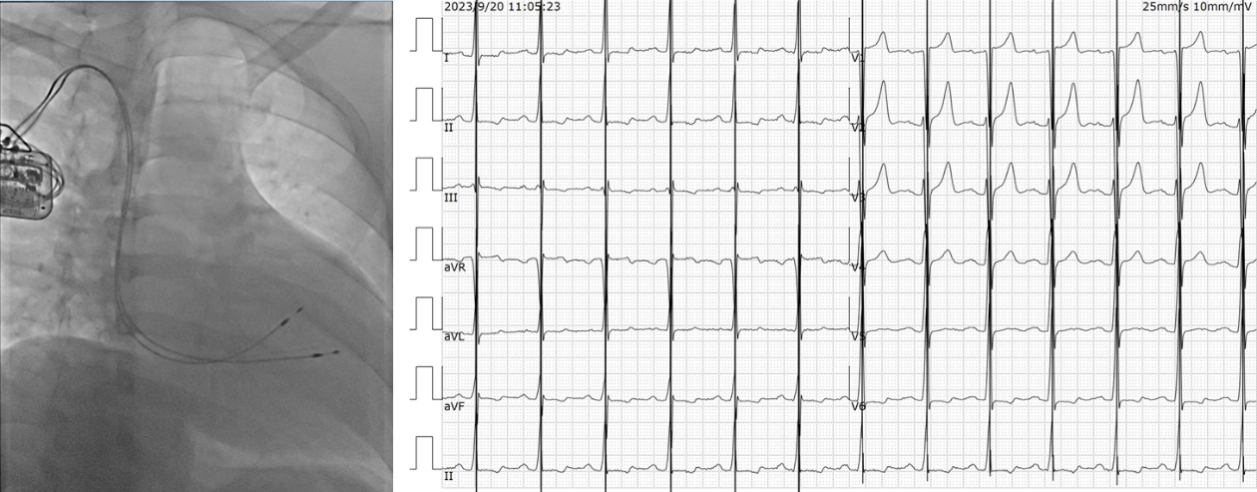

上图所示病例是一位32岁的扩张性心肌病患者,其左室射血分数(LVEF)仅为29%,在植入了心肌收缩力调节器(CCM)一个月后随访,自觉胸闷及气促等症状明显缓解,对该病例的随访还在进行中。